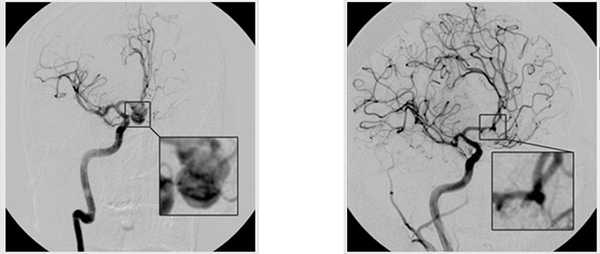

Несмотря на кардинальную разницу в клиническом течении заболевания, у этих больных с сугубо хирургической точки зрения есть много общего. Главное — определение «приоритетной» аневризмы, т. е. той, которая подлежит хирургическому вмешательству в первую очередь. У больного с множественными аневризмами в холодном периоде кровоизлияния это аневризма, которая была причиной кровоизлияния. Выявить ее удается с учетом очаговой неврологической симптоматики и применения современных методов рентгенодиагностики в 99—100% случаев [7, 8]. Как правило, это самая большая аневризма у данного больного, часто с неровными контурами и дивертикулами. Именно эти аневризмы, с наибольшим риском разрыва подлежат выключению из кровотока в первую очередь. Во всех случаях после выключения приоритетной аневризмы из кровотока с помощью того или иного метода решается задача выключения максимального количества аневризм за одно хирургическое вмешательство. В рамках микрохирургических операций это возможно при ипсилатеральных аневризмах передних отделов виллизиева круга, которые могут быть клипированы по ходу основного хирургического доступа, иногда возможно и при аневризмах противоположной стороны с применением контралатеральных доступов. При эндовазальных вмешательствах после выключения приоритетной аневризмы ставится задача эндовазального выключения оставшихся аневризм. Особого внимания требуют сложные аневризмы вертебробазилярного бассейна, которые предпочтительно выключать эндовазальным способом как при применении ППНС, так и при их окклюзии микроспиралями со стент-ассистенцией, которые требуют и во время операции, и в ближайшем послеоперационном периоде проведения антиагрегантной терапии. При невозможности выключения эндовазальным способом оставшихся аневризм они могут быть выключены микрохирургическим способом через 2—3 мес во избежание риска послеоперационных гематом. Опыт НМИЦ нейрохирургии им. акад. Н.Н. Бурденко показывает, что создавшиеся клинические ситуации не увеличивают риск возможного разрыва оставшихся не выключенных из кровотока аневризм. Мы не нашли подтверждения подобных опасений и в литературе.